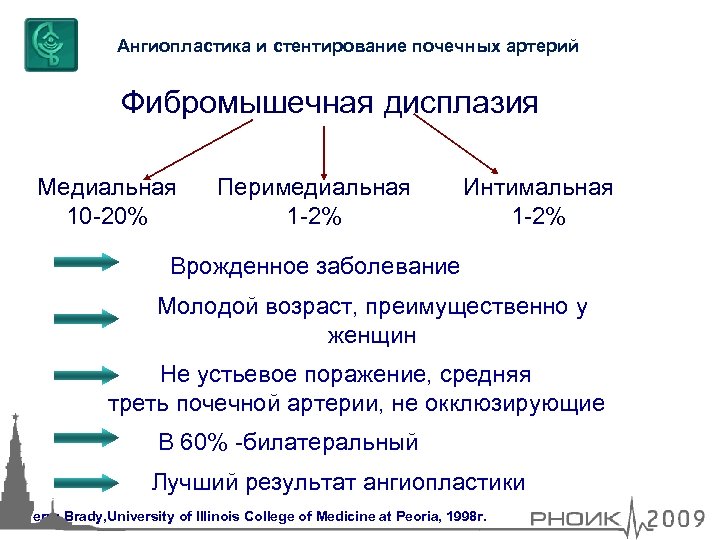

Ангиопластика и стентирование почечных артерий Фибромышечная дисплазия Медиальная 10 -20% Перимедиальная 1 -2% Интимальная 1 -2% Врожденное заболевание Молодой возраст, преимущественно у женщин Не устьевое поражение, средняя треть почечной артерии, не окклюзирующие В 60% -билатеральный Лучший результат ангиопластики Terry Brady, University of Illinois Сollege of Medicine at Peoria, 1998 г.

Ангиопластика и стентирование почечных артерий Фибромышечная дисплазия Медиальная 10 -20% Перимедиальная 1 -2% Интимальная 1 -2% Врожденное заболевание Молодой возраст, преимущественно у женщин Не устьевое поражение, средняя треть почечной артерии, не окклюзирующие В 60% -билатеральный Лучший результат ангиопластики Terry Brady, University of Illinois Сollege of Medicine at Peoria, 1998 г.